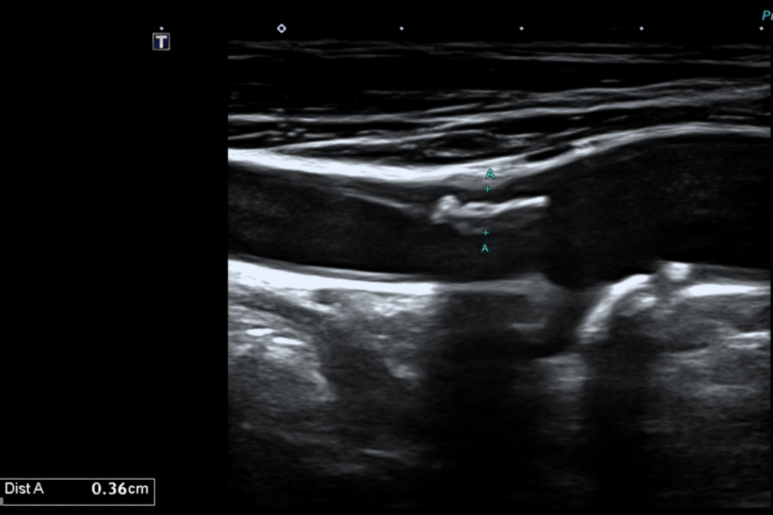

우측 경동맥에 하얗게 보이는 석회화가 많이 껴있는 것을 확인할 수 있고, 이로 인해 직격이 40% 정도 좁아져 경동맥 협착으로 판단하여, 추적관찰 권고함.

• 경동맥 초음파 결과: 경동맥 협착 경동맥 초음파 결과: 경동맥 협착